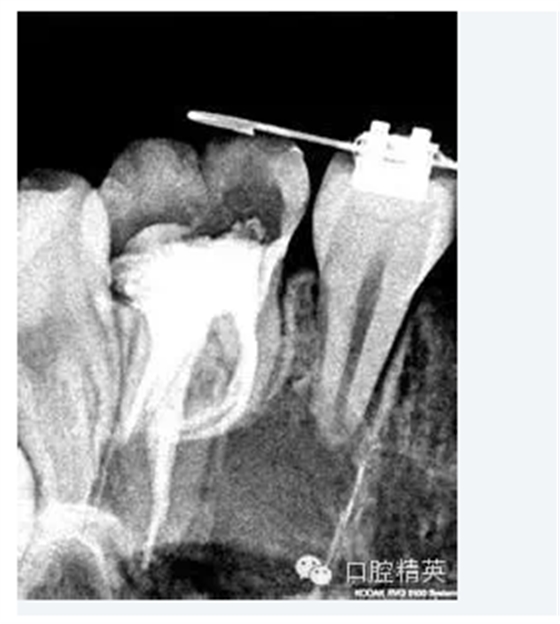

5.根管髓腔部分的預(yù)先擴大可以幫助牙醫(yī)做出更明確的診斷。預(yù)先擴大的根管髓腔部分可以容納較大型號的金屬根管擴大器,X光片顯示更清晰;由于接觸頭更容易的與髓腔牙本質(zhì)接觸,電子根尖定位器的顯示也更明確。

3.工作長度經(jīng)驗豐富的臨床牙醫(yī)可以根據(jù)以往經(jīng)驗來判斷根管的工作長度。作為輔助手段,電子根尖定位器能提供更準(zhǔn)確、更可信、更有價值的工作長度信息,甚至在根管鈣化明顯或彎曲嚴(yán)重的病例也能對根尖孔進行準(zhǔn)確定位。在操作過程中,切記一點,電子根尖定位器只能作為X片的輔助手段,而不可完全代替?zhèn)鹘y(tǒng)X片的作用。當(dāng)根據(jù)X線片(RT)及電子根尖定位器,根管的工作長度都已得到準(zhǔn)確確定后,即可采取多種方法對根管的根尖側(cè)1/3進行最后的擴大完成。